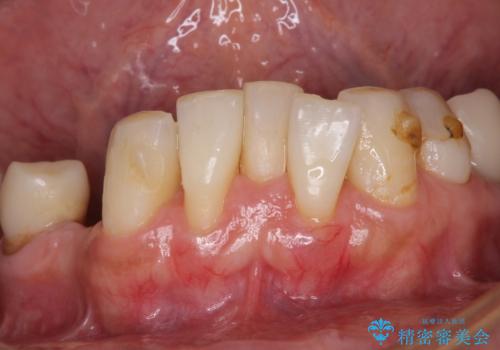

- 以前通院していた医院で、奥歯のインプラント埋入、前歯部のインビザライン矯正を行ったものの、そのまま放置してしまったとのことで来院された患者様です。

下顎前歯や上顎奥歯などをワイヤー装置により部分矯正を行い、歯列を整えた上でインプラン部分を含めてオールセラミッククラウンにて補綴治療を行うこととしました。

インプラント上の仮歯がボロボロになり、前歯に非常に負担のかかる状態であったため、早急に奥歯の仮歯を修復し、矯正治療、奥歯の補綴治療、前歯の補綴治療と順々に進めて行きました。